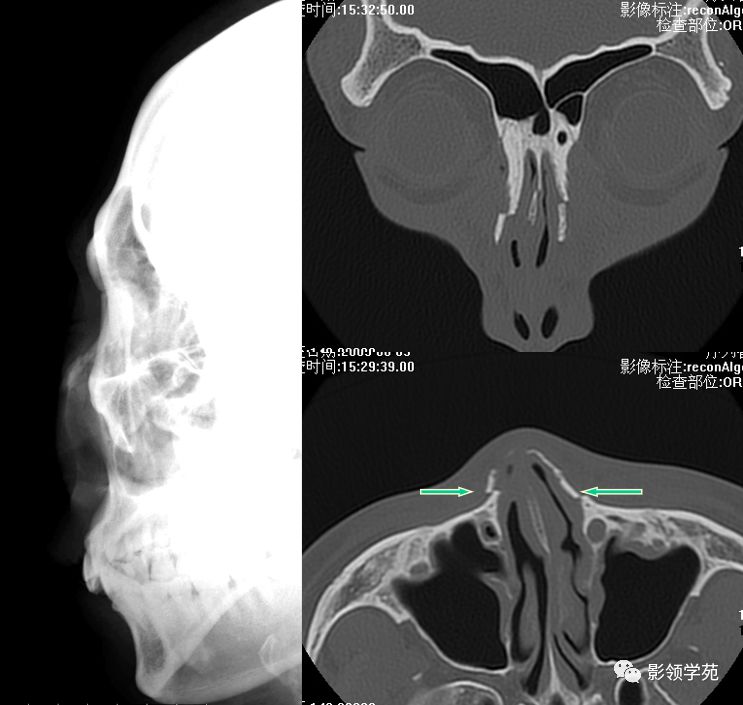

线性骨折 粉碎骨折

右侧鼻骨线形骨折

鼻骨线形骨折

左侧鼻骨线形骨折

右侧鼻骨骨折

左上颌骨额突骨折

双侧鼻骨骨折

双侧上颌骨额突骨折